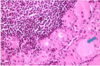

Know this image.

yeah.